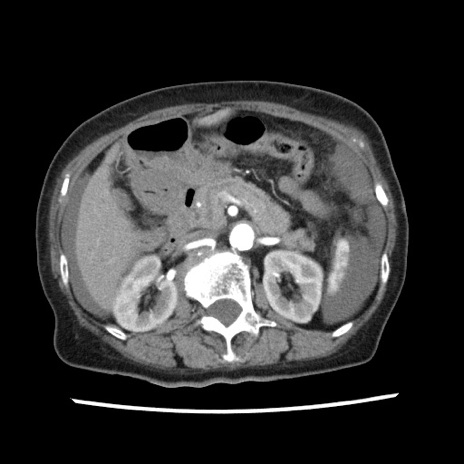

症例1(横断像)

【症例】80歳代女性

【主訴】腹痛

【現病歴】8時間前から腹痛あり来院。

【既往歴】糖尿病、脂質異常症、子宮体癌にて子宮全摘術

【身体所見】意識清明・会話良好だが腹痛で苦悶様、全腹部にわたって反跳痛と圧痛あり

【データ】WBC 13600、CRP 0.14、LDH 224、CK 90